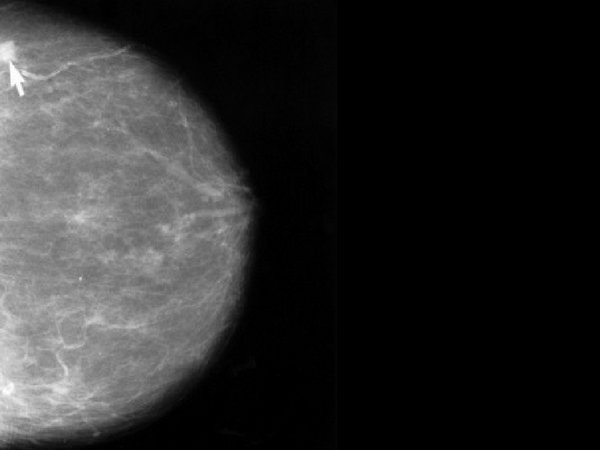

Treatment Options For Fibrocystic Breast Disease

There are several treatment options for fibrocystic breasts. Read to know the best treatment for fibrocystic breast disease.

Fibrocystic breasts are characterized by the lumpiness and usual discomfort in one or both breasts. The lumpiness is due to small breast masses or breast cysts.

This condition is known to be very common and benign. Fibrocystic breast condition is the most common cause of lumpy breasts and affects more than 60% of women.

8. Clinical Breast Exam:

Your doctor needs to check for unusual areas by visually and manually examining your breasts and the lymph nodes located in your lower neck and the underarm.

9. Fine-Needle Aspiration:

For a breast lump that feels like a cyst, your doctor may try fine-needle aspiration to see if fluid can be withdrawn from the lump.